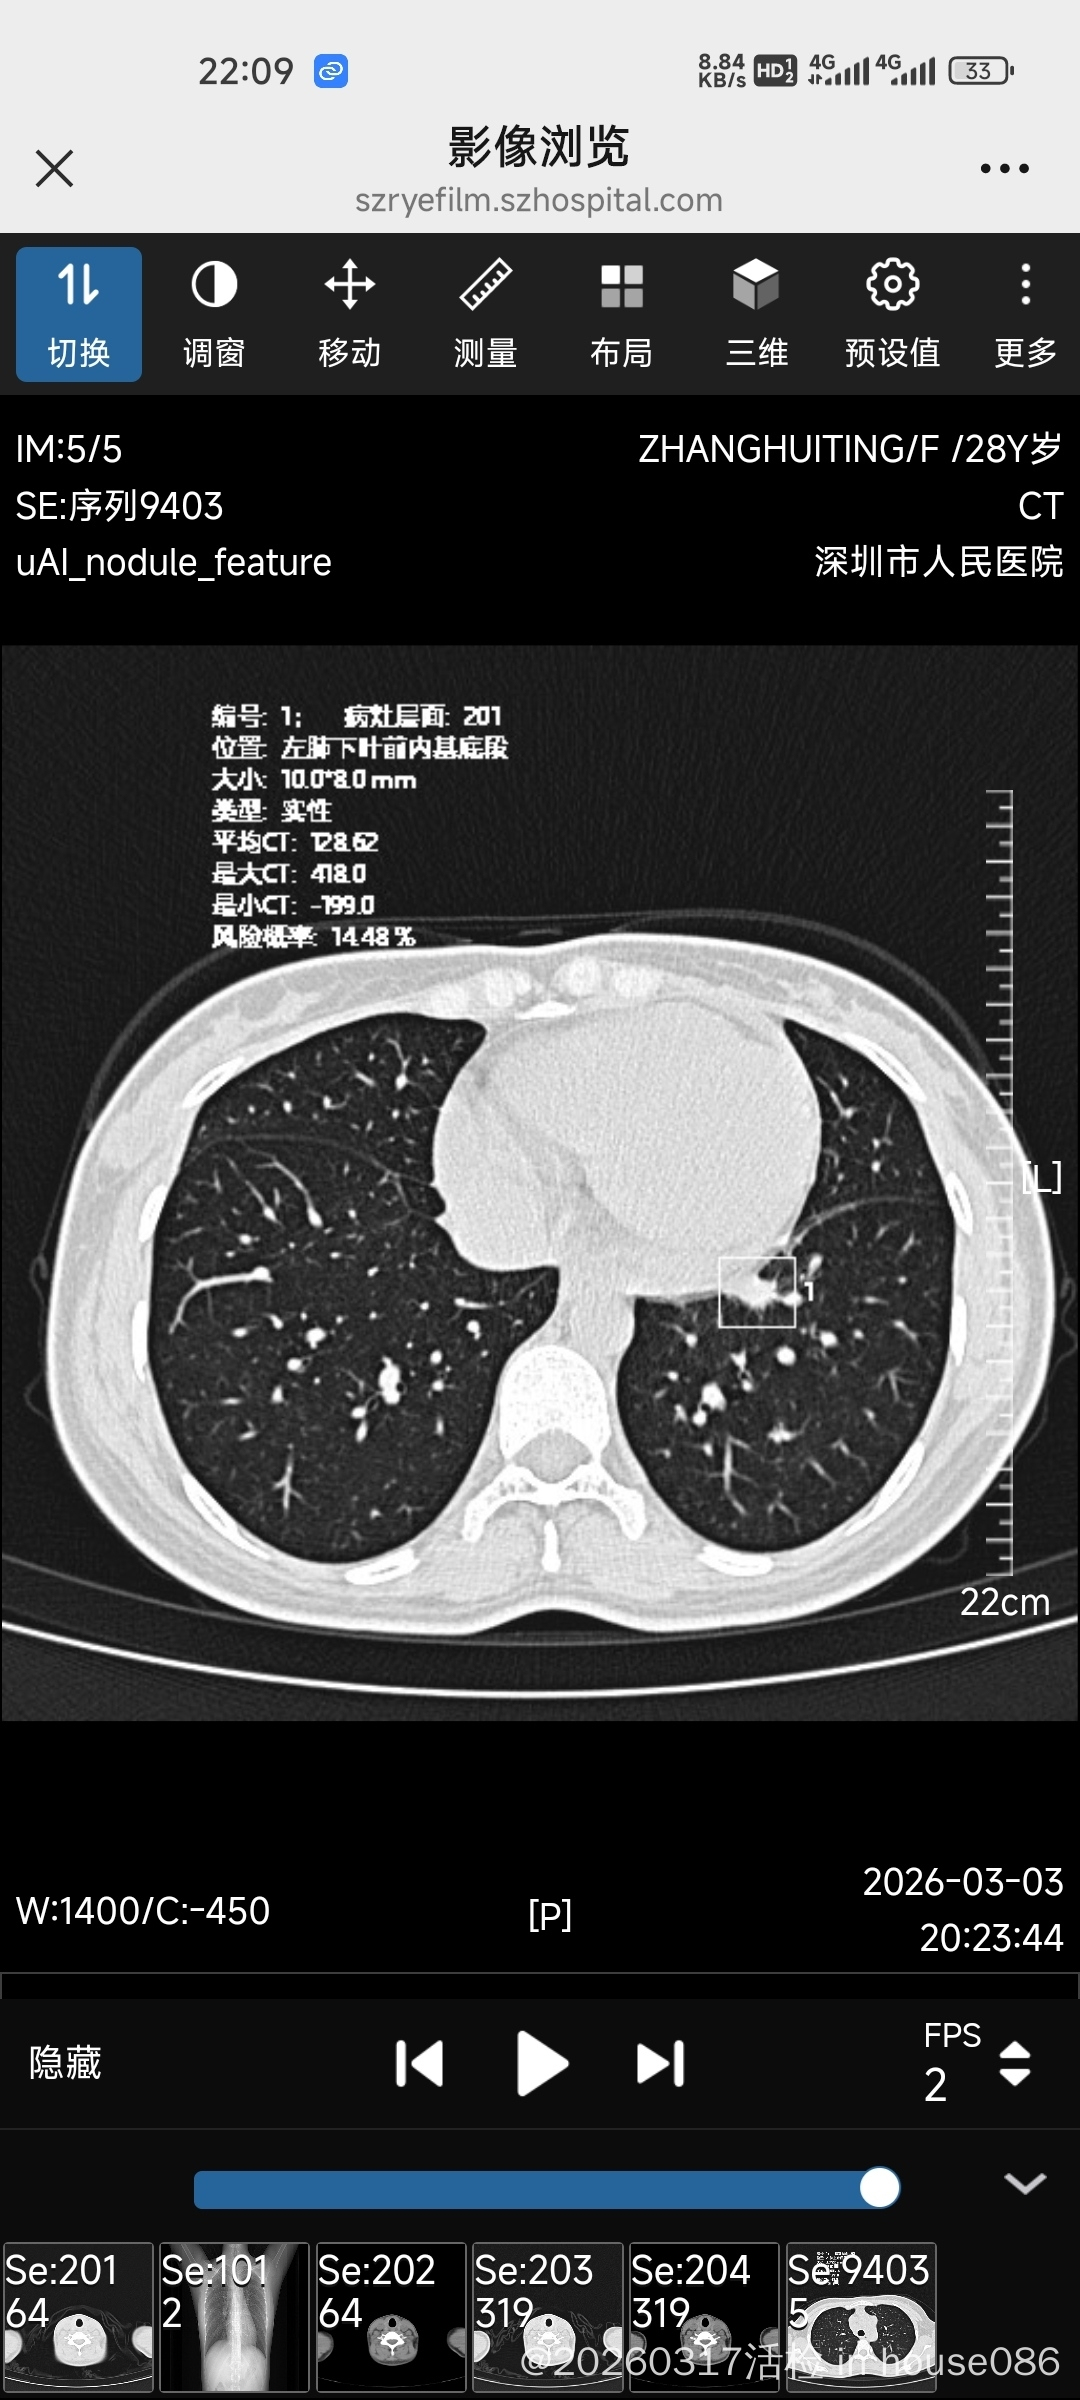

24年冬天腿痒了一年,25年冬天好了,26年1月份左右脖子长了几颗淋巴结,刚开始长出来的时候很疼,有些消了,有一个大的在锁骨上有点硬,没有消,然后元宵节期间开始咳嗽到现在,去深圳市人民医院急诊查了一下CT双肺多发实性结节,双纵膈双肺门淋巴结肿大,胸外科医生说肺部恶性概率小。

这次取了活检,医生说结节病和淋巴瘤概率各一半,这次冰冻和石蜡结果都显示可见异型细胞团,请大家看看怎么办好,还在等市人民医院的免疫组化中...